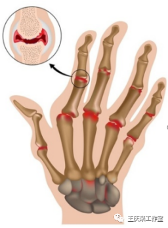

另外类风湿性关节炎造成的关节变形,具有独特之处,如:手指天鹅颈样、钮扣花样畸形。而骨性关节炎则没有这种典型的表现。